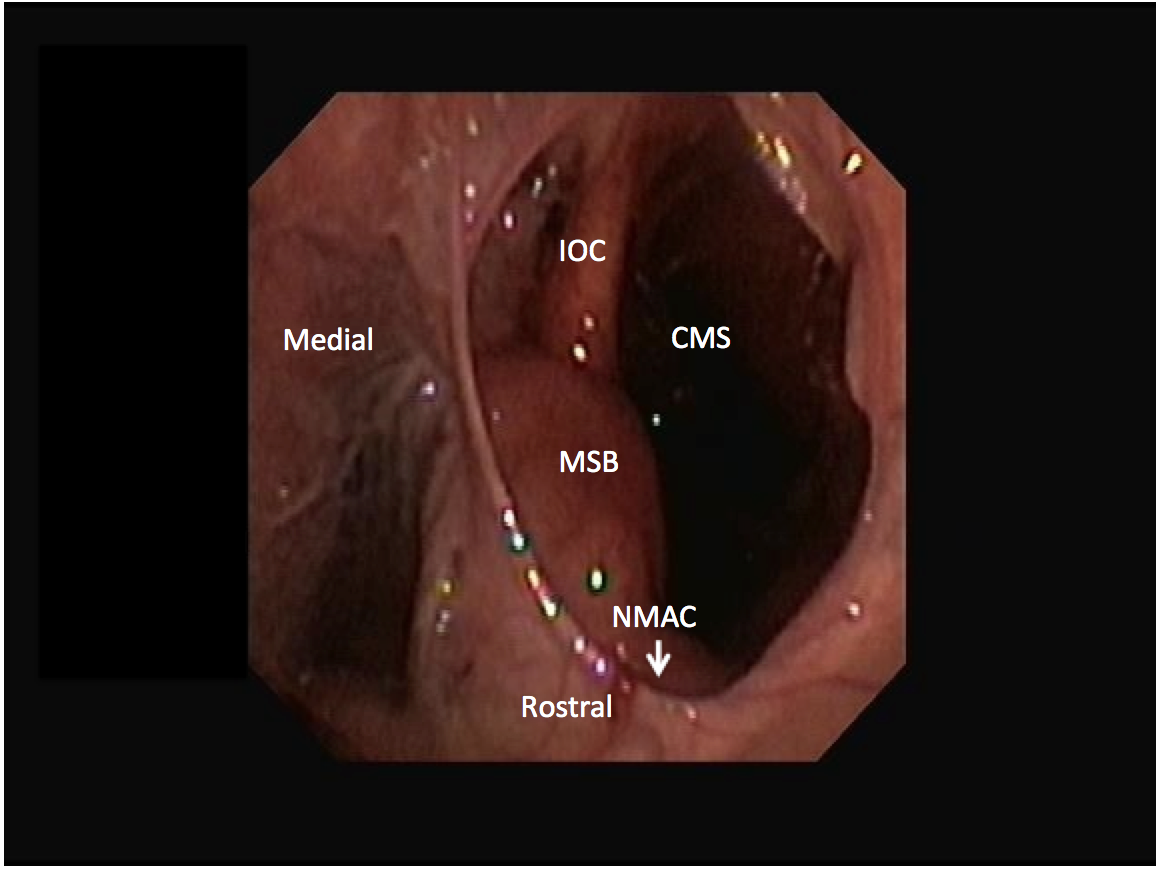

The rostral maxillary sinus and the ventral conchal sinus are frequent sites of infection caused by apical dental infection or inspissated exudate, respectively. However, these sinuses are not directly accessible from trephine holes into the conchofrontal or caudal maxillary sinuses (Figure 1). The rostral maxillary sinus can be examined independently through a rostrally placed maxillary bone trephination. However, this is generally not recommended in young horses to avoid iatrogenic damage to the reserve crowns of the ninth and 10th maxillary teeth. The ventral conchal sinus and rostral maxillary sinus can both be evaluated through a portal into the conchofrontal or caudal maxillary sinuses after fenestration of the cartilaginous maxillary septal bulla (formerly termed ventral conchal bulla). The maxillary septal bulla is desensitized with topical local anesthetics and fenestrated with endoscopic guidance using a Ferris-Smith arthroscopic rongeur, crocodile forceps, or diode laser via the same portal as the endoscope (Figure 2). If fenestration of the bulla causes bleeding that obscures observation, sinoscopy should be repeated after 24 to 48 hours. Lavage of all compartments is possible after fenestrating the bulla.4

Figure 1.